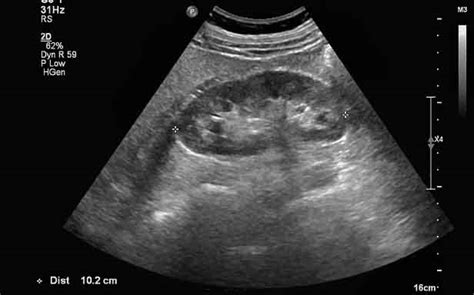

Nell'era della medicina basata sull'evidenza e della tecnologia avanzata, la manovra di Giordano non è più l'unico né il principale strumento diagnostico per le patologie renali. L'ecografia renale e delle vie urinarie è diventata un esame di prima linea per la sua non invasività, la disponibilità e la capacità di visualizzare i reni, le vie urinarie e la presenza di dilatazione (idronefrosi) o calcoli visibili.

La Tomografia Computerizzata (TC) senza mezzo di contrasto è considerata il gold standard per la diagnosi della calcolosi urinaria, in quanto è in grado di visualizzare anche calcoli di piccole dimensioni e di valutare la presenza di ostruzioni.